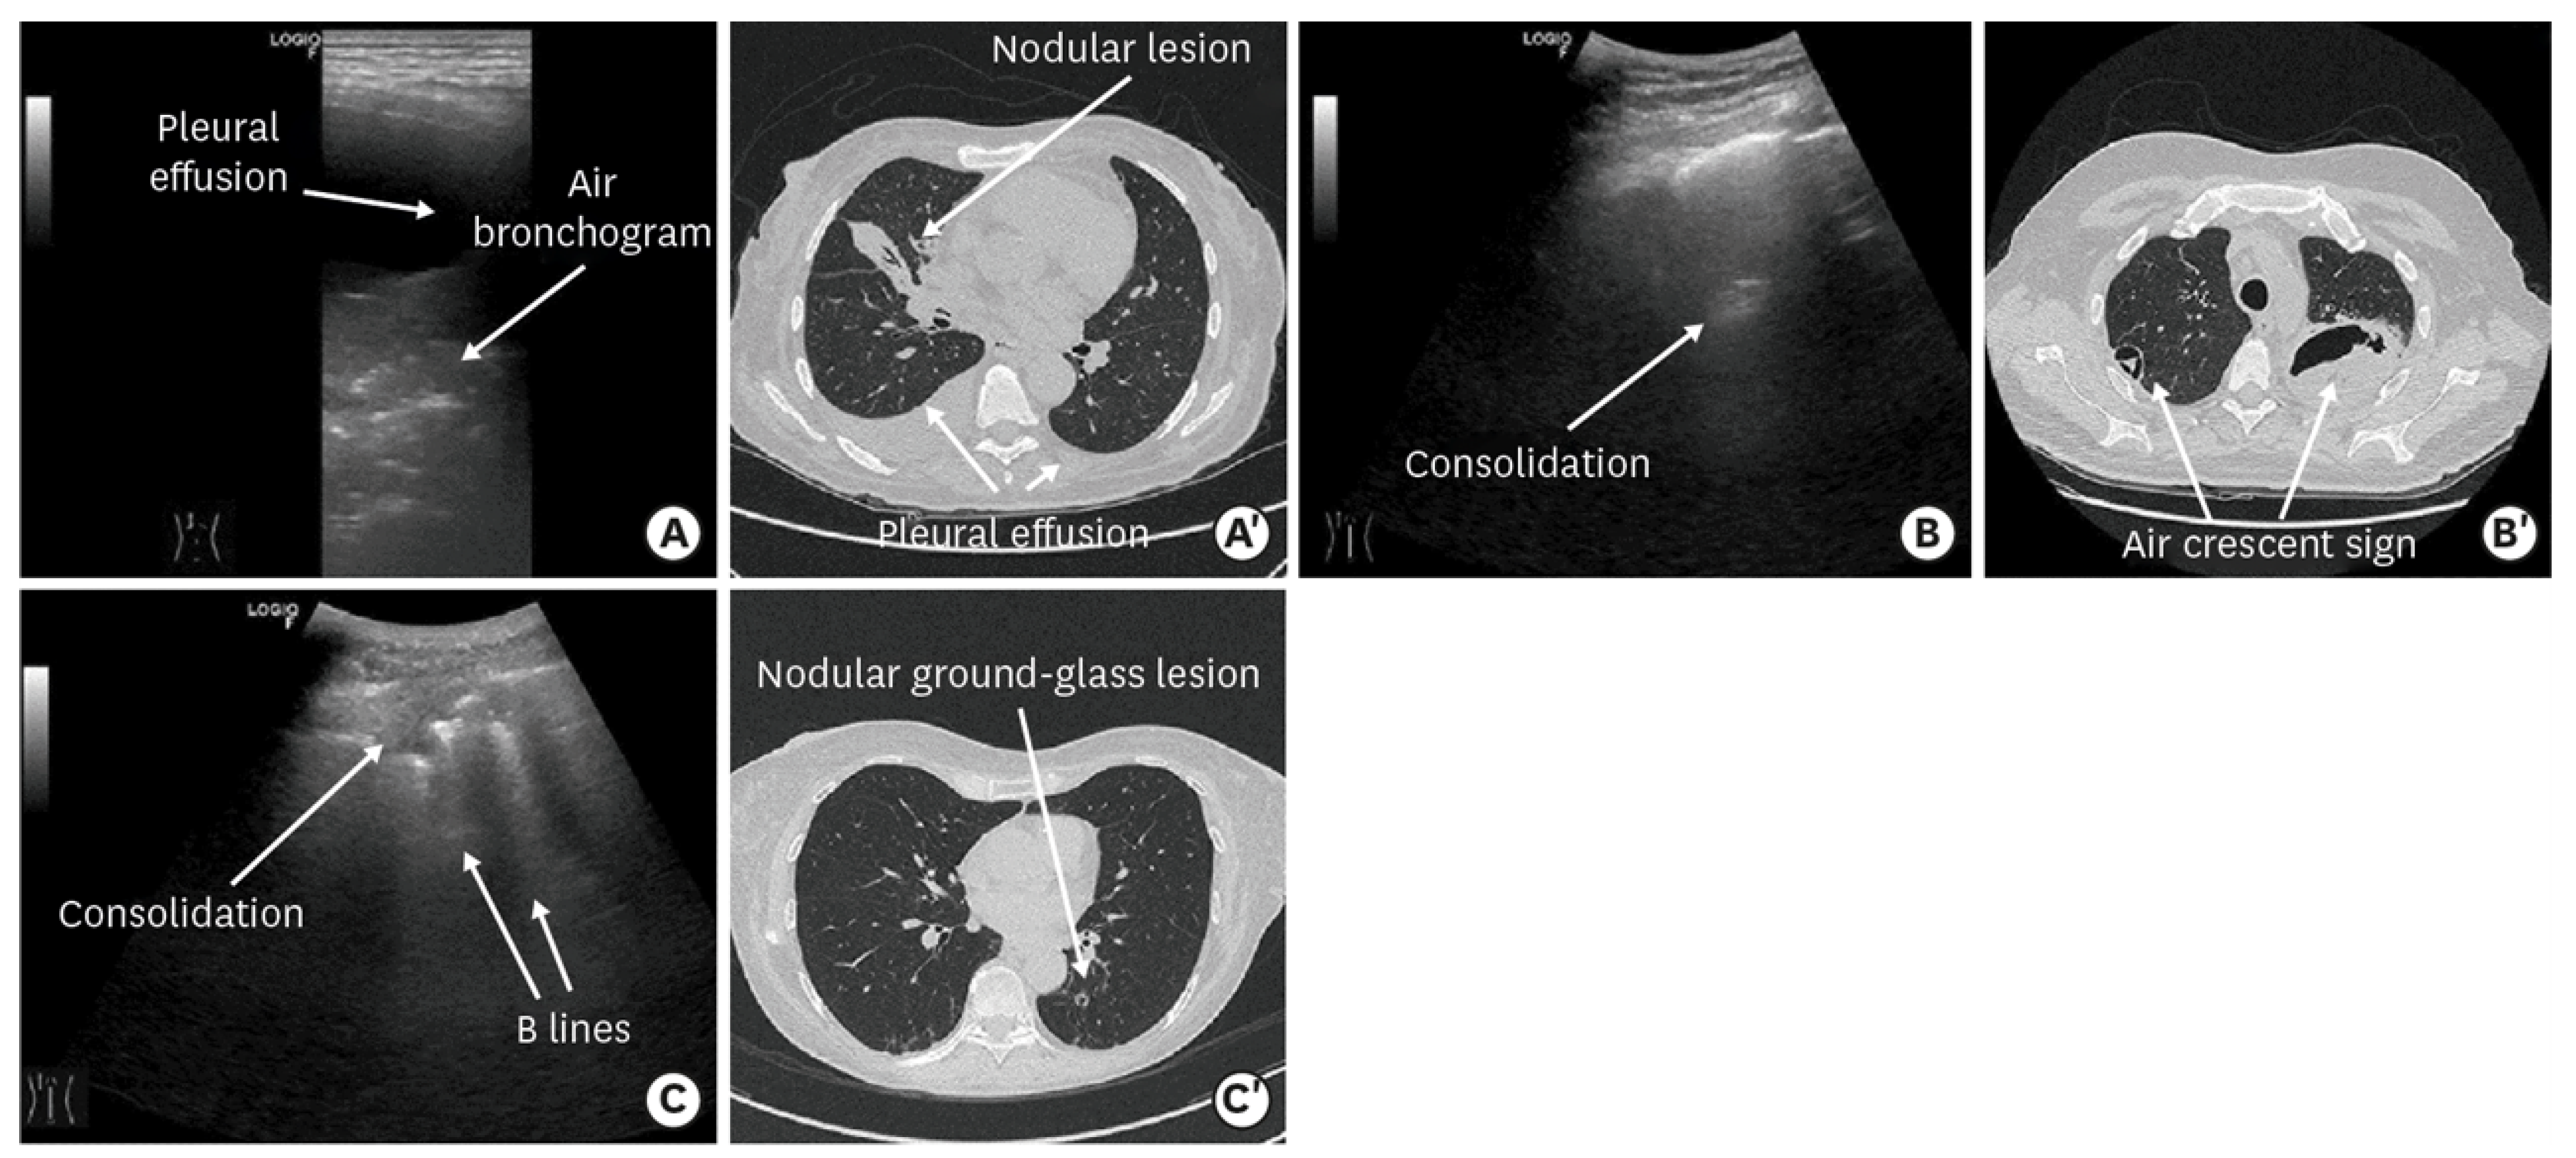

- Li, S.; Zhang, Q.L.; Guo, R.J.; Lv, X.Z.; Yang, X. Quantitative evaluation and significance of ultrasound in bronchoalveolar lavage for lung consolidation in children with severe mycoplasma pneumonia. Transl. Pediatr. 2021, 10, 2325–2334. [Google Scholar] [CrossRef]

- Tripaldi, C.; Polito, M.; Iacoviello, O.; Basile, V.; De Bellis, T.; Fortunato, M.; Laforgia, F.; Scalini, E.; Silletti, M.; Lofù, I. Ultrasound Studies on Mycoplasma Bronchopneumonia. J. Curr. Med. Res. Opin. 2021, 5, 1301–1315. [Google Scholar] [CrossRef]

- Buonsenso, D.; Musolino, A.; Ferro, V.; De Rose, C.; Morello, R.; Ventola, C.; Liotti, F.M.; De Sanctis, R.; Chiaretti, A.; Biasucci, D.G.; et al. Role of lung ultrasound for the etiological diagnosis of acute lower respiratory tract infection (ALRTI) in children: A prospective study. J. Ultrasound 2022, 25, 185–197. [Google Scholar] [CrossRef]

- Liu, G.; Wang, G.; Yang, Z.; Liu, G.; Ma, H.; Lv, Y.; Ma, F.; Zhu, W. A Lung Ultrasound-Based Nomogram for the Prediction of Refractory Mycoplasma pneumoniae Pneumonia in Hospitalized Children. Infect. Drug. Resist. 2022, 31, 6343–6355. [Google Scholar] [CrossRef]